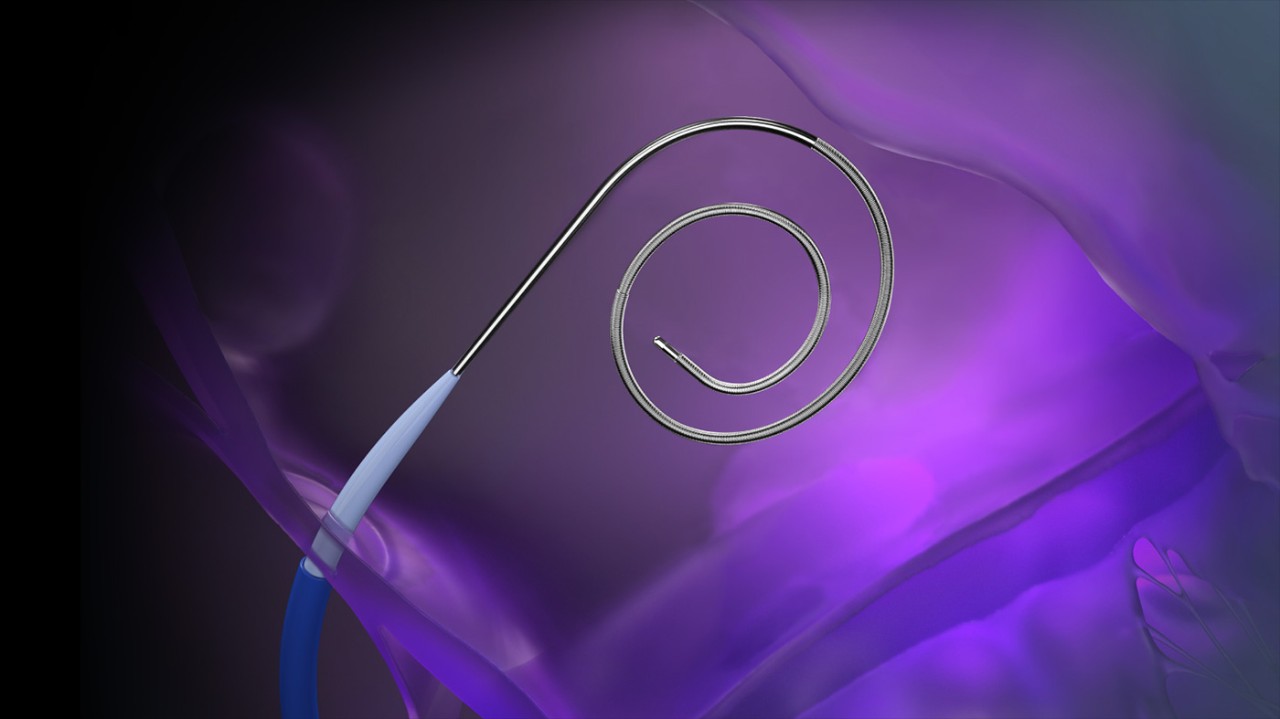

• VersaCross RF Wire (j-tip or pigtail)

VersaCross RF Wire

Tip configurationsJ-tip, pigtail

Curve shape9 mm (j-tip), 24 mm (pigtail)

Wire diameter0.035 in (0.89 mm)

Overall length180 cm, 230 cm

VersaCross RF Wire in j-tip and pigtail configurations.

RF wire length: 180 cm, 230 cm

Wire diameter: 0.035 in (0.89 mm)

Curve diameter: 9 mm (j-tip), 24 mm (pigtail)